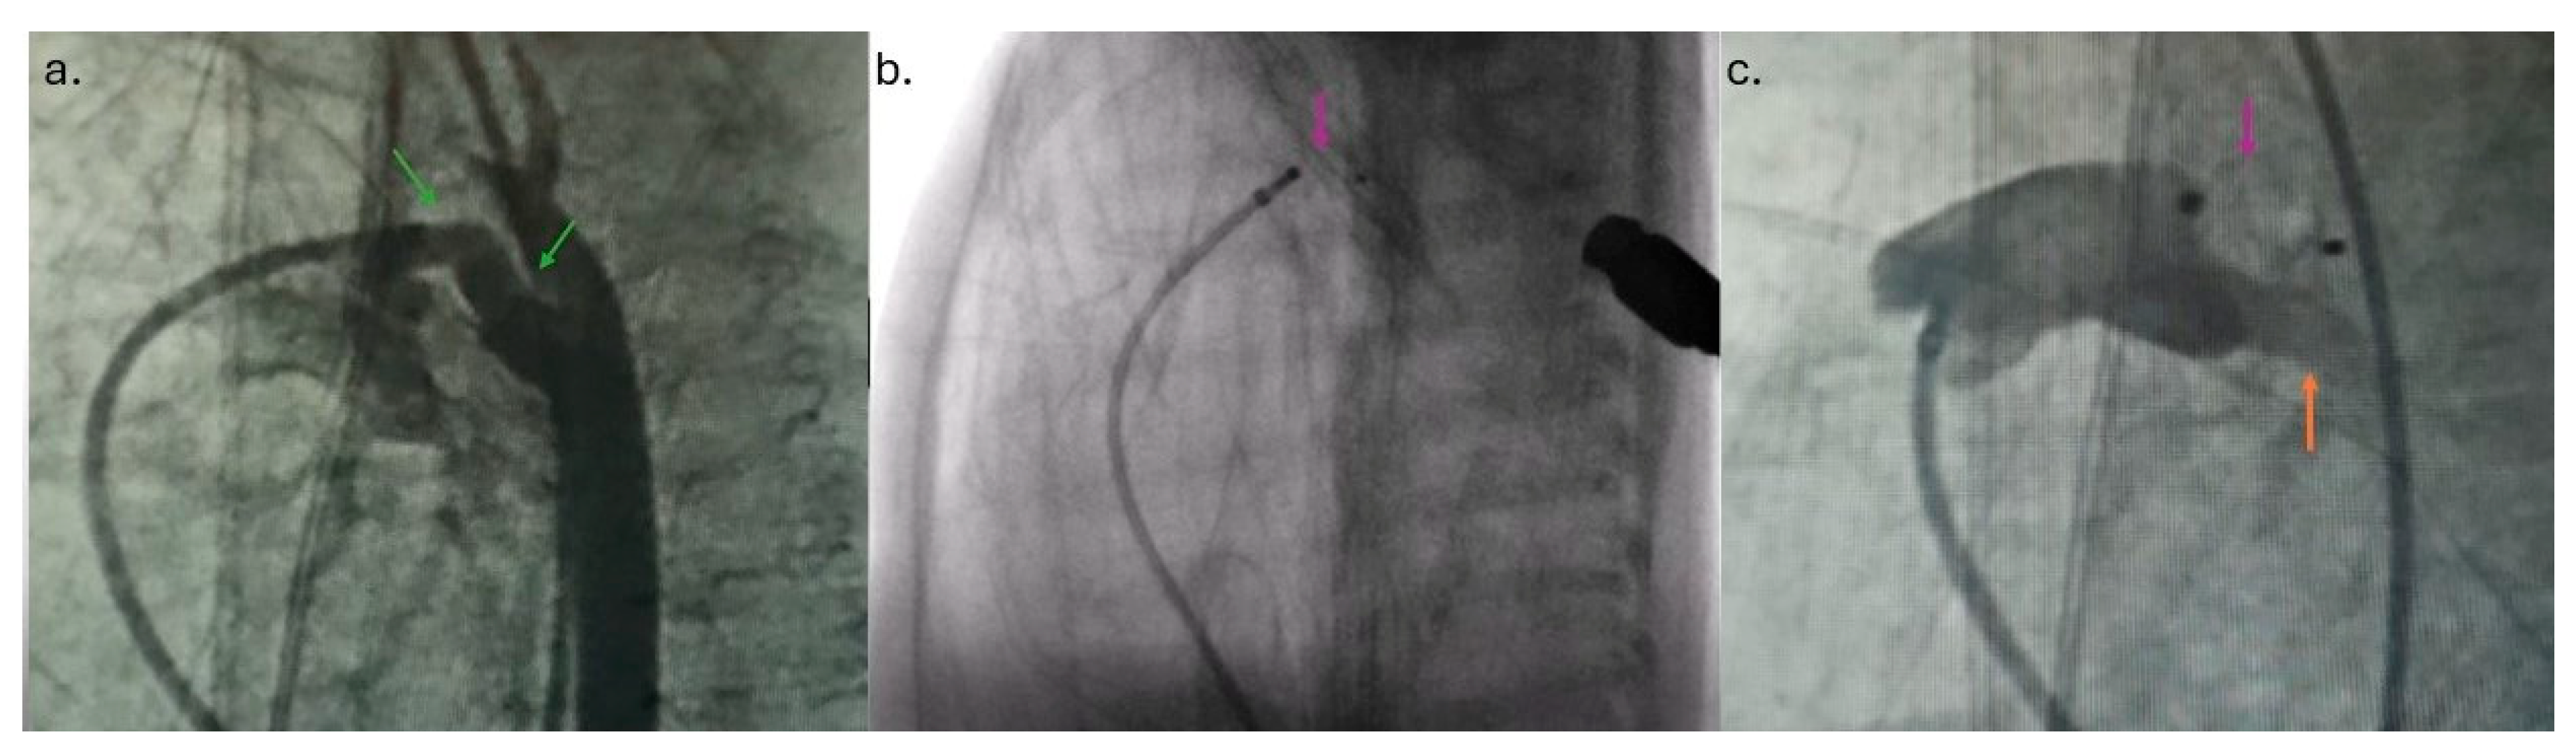

The intervention was performed in a catheterization room under general anesthesia. The neonatal transport team transferred the patients to the Cath Lab. Both patients were on mechanical ventilation, so the position of the ETT was checked using fluoroscopy at the start of the procedure. To prevent oxygen-free radical damage to end organs, the goal oxygen saturation was 89–93% [7]. An air heater and plastic drape cover prevented hypothermia. A standard 4 Fr introducer sheath is placed in the right femoral vein using a 20-gauge needle, floppy-tipped 0.018 guide wire, and standard Seldinger technique using ultrasound guidance. The right Judkins catheter and 0.035″ Terumo guide wire were fed across the femoral vein, lower vena cava, right atrium, right ventricle, pulmonary artery, and PDA placed in the descending aorta. Across the right Judkins catheter, a 0.018′′ floppy tipped wire with a “hockey stick” curve was introduced in the aorta, and the right Judkins catheter was then exchanged for the Torqvue LP delivery catheter (Abbott, MN, USA) (0.046″). Biplane aortography [6] was performed in anteroposterior and left lateral planes [4]. The angiography (1.5 mL of contrast) revealed PDA Krichenco type E (Figure 2a) [8]. Before the aortography, a naso-gastric tube was filled with contrast to mark the aortic end of the PDA. In the first patient, the duct diameter on the pulmonary end was measured at 2.4 mm, and the length was 9 mm. In the second case, the pulmonary end diameter was 2.7 mm, and the length was 12 mm. We decided to use APO 9-PDAP-04-02-L and 9-PDAP-04-04-L, respectively. The entire device, with both retention discs, was implanted within the duct (Figure 2b). Before realizing the device, TTE pointed out adequate device position without descending aorta, left pulmonary branch obstruction, and a residual shunt (Figure 1c,d). Control angiography after the device was realized confirmed adequate APO position (Figure 2c). Prophylactic antibiotics and a heparin bolus (100 IU/kg) were administered. The intervention was uneventful; the fluoroscopy lasted 5 min, and we spent 3 mL of contrast. In the third case, epinephrine was continuously administered throughout the entire procedure.

Figure 2. (a) Angiogram in the left lateral position indicated widely open ductus arteriosus (green arrow) and both pulmonary branches. (b) The entire Amplatzer Piccolo Occluder (pink arrow) was placed into ductus arteriosus. (c) Pulmonary artery angiogram after the device was released (orange arrow—left pulmonary artery).